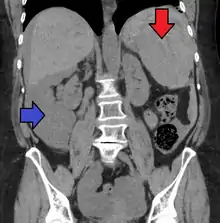

| Spleen ruptured by trauma | |

Splenic rupture is usually evaluated by FAST ultrasound of the abdomen.[4] Generally this is not specific to splenic injury; however, it is useful to determine the presence of free floating blood in the peritoneum.[4] A diagnostic peritoneal lavage, while not ideal, may be used to evaluate the presence of internal bleeding a person who is hemodynamically unstable.[5] The FAST exam typically serves to evaluate the need to perform a CT scan.[5] Computed tomography with IV contrast is the preferred imaging study as it can provide high quality images of the full peritoneal cavity.[4]